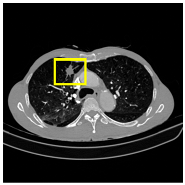

3.4.2. Representative Cases with Segmentation Challenges on the MEF-PN35 Dataset

To complement the quantitative evaluation, we present a set of representative cases from the clinical dataset that exhibited typical segmentation challenges. These cases were selected to reflect diverse morphological characteristics observed in pulmonary nodules, such as spiculated boundaries, small size, vessel adherence, pleural attachment, cavitation, and clear isolation. Rather than aiming for exhaustive categorization, our intent is to highlight a range of practical difficulties encountered in real-world scenarios and to qualitatively assess how different boundary-aware loss functions respond to these variations. Each challenge is labeled (C1) through (C5) in Table 10 and is consistently referenced in the corresponding detailed illustrations that follow.

Following the summary in Table 11, we present detailed visual comparisons for selected representative cases, each corresponding to a specific segmentation challenge. These cases are consistently labeled using the Challenge ID (CID) codes defined in Table 9 to facilitate cross-referencing between the summary and the case illustrations. Each table reports segmentation results across three loss configurations (Sobel, Laplacian, and Hausdorff) using five columns. Loss indicates the boundary loss formulation applied in each case, where Dice loss is combined with a boundary term computed using Sobel, Laplacian, or Hausdorff operators. The Segmentation Result column shows four images side by side: the input CT patch, the manual ground truth, the model prediction, and a color-coded difference map between ground truth and prediction. In this map, green indicates true positives, blue represents true negatives, red corresponds to false positives, and yellow denotes false negatives. The final column, Attention Map, presents Grad-CAM visualizations derived from one of the Adaptive Attention Fusion (AAF) layers in the encoder path. These maps illustrate the spatial focus of the model, with red/yellow regions indicating strong attention and lighter or neutral tones indicating lower activation. All six cases are presented in detail in Table 11, Table 12 and Table 13, providing a comprehensive qualitative analysis of how each loss configuration performs under specific segmentation challenges observed in real clinical data.